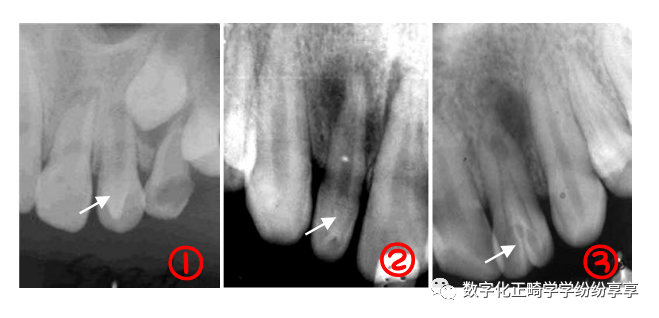

牙外伤 Traumatic Injuries of the teeth:

牙折

曲面断层片怎么看正畸【曲面断层片(全景片)】如何解读和查看:牙周?牙体?牙髓?关节?_https://www.jmylbn.com_新闻资讯_第20张

牙根折裂

曲面断层片怎么看正畸【曲面断层片(全景片)】如何解读和查看:牙周?牙体?牙髓?关节?_https://www.jmylbn.com_新闻资讯_第21张

牙脱位

曲面断层片怎么看正畸【曲面断层片(全景片)】如何解读和查看:牙周?牙体?牙髓?关节?_https://www.jmylbn.com_新闻资讯_第22张